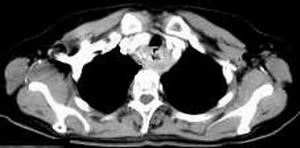

女,61岁,吞咽困难(包括开水)已久。

食道中上段癌并锁骨上窝淋巴结转移.

食道中上段中分化鳞癌伴锁骨上淋巴结转移